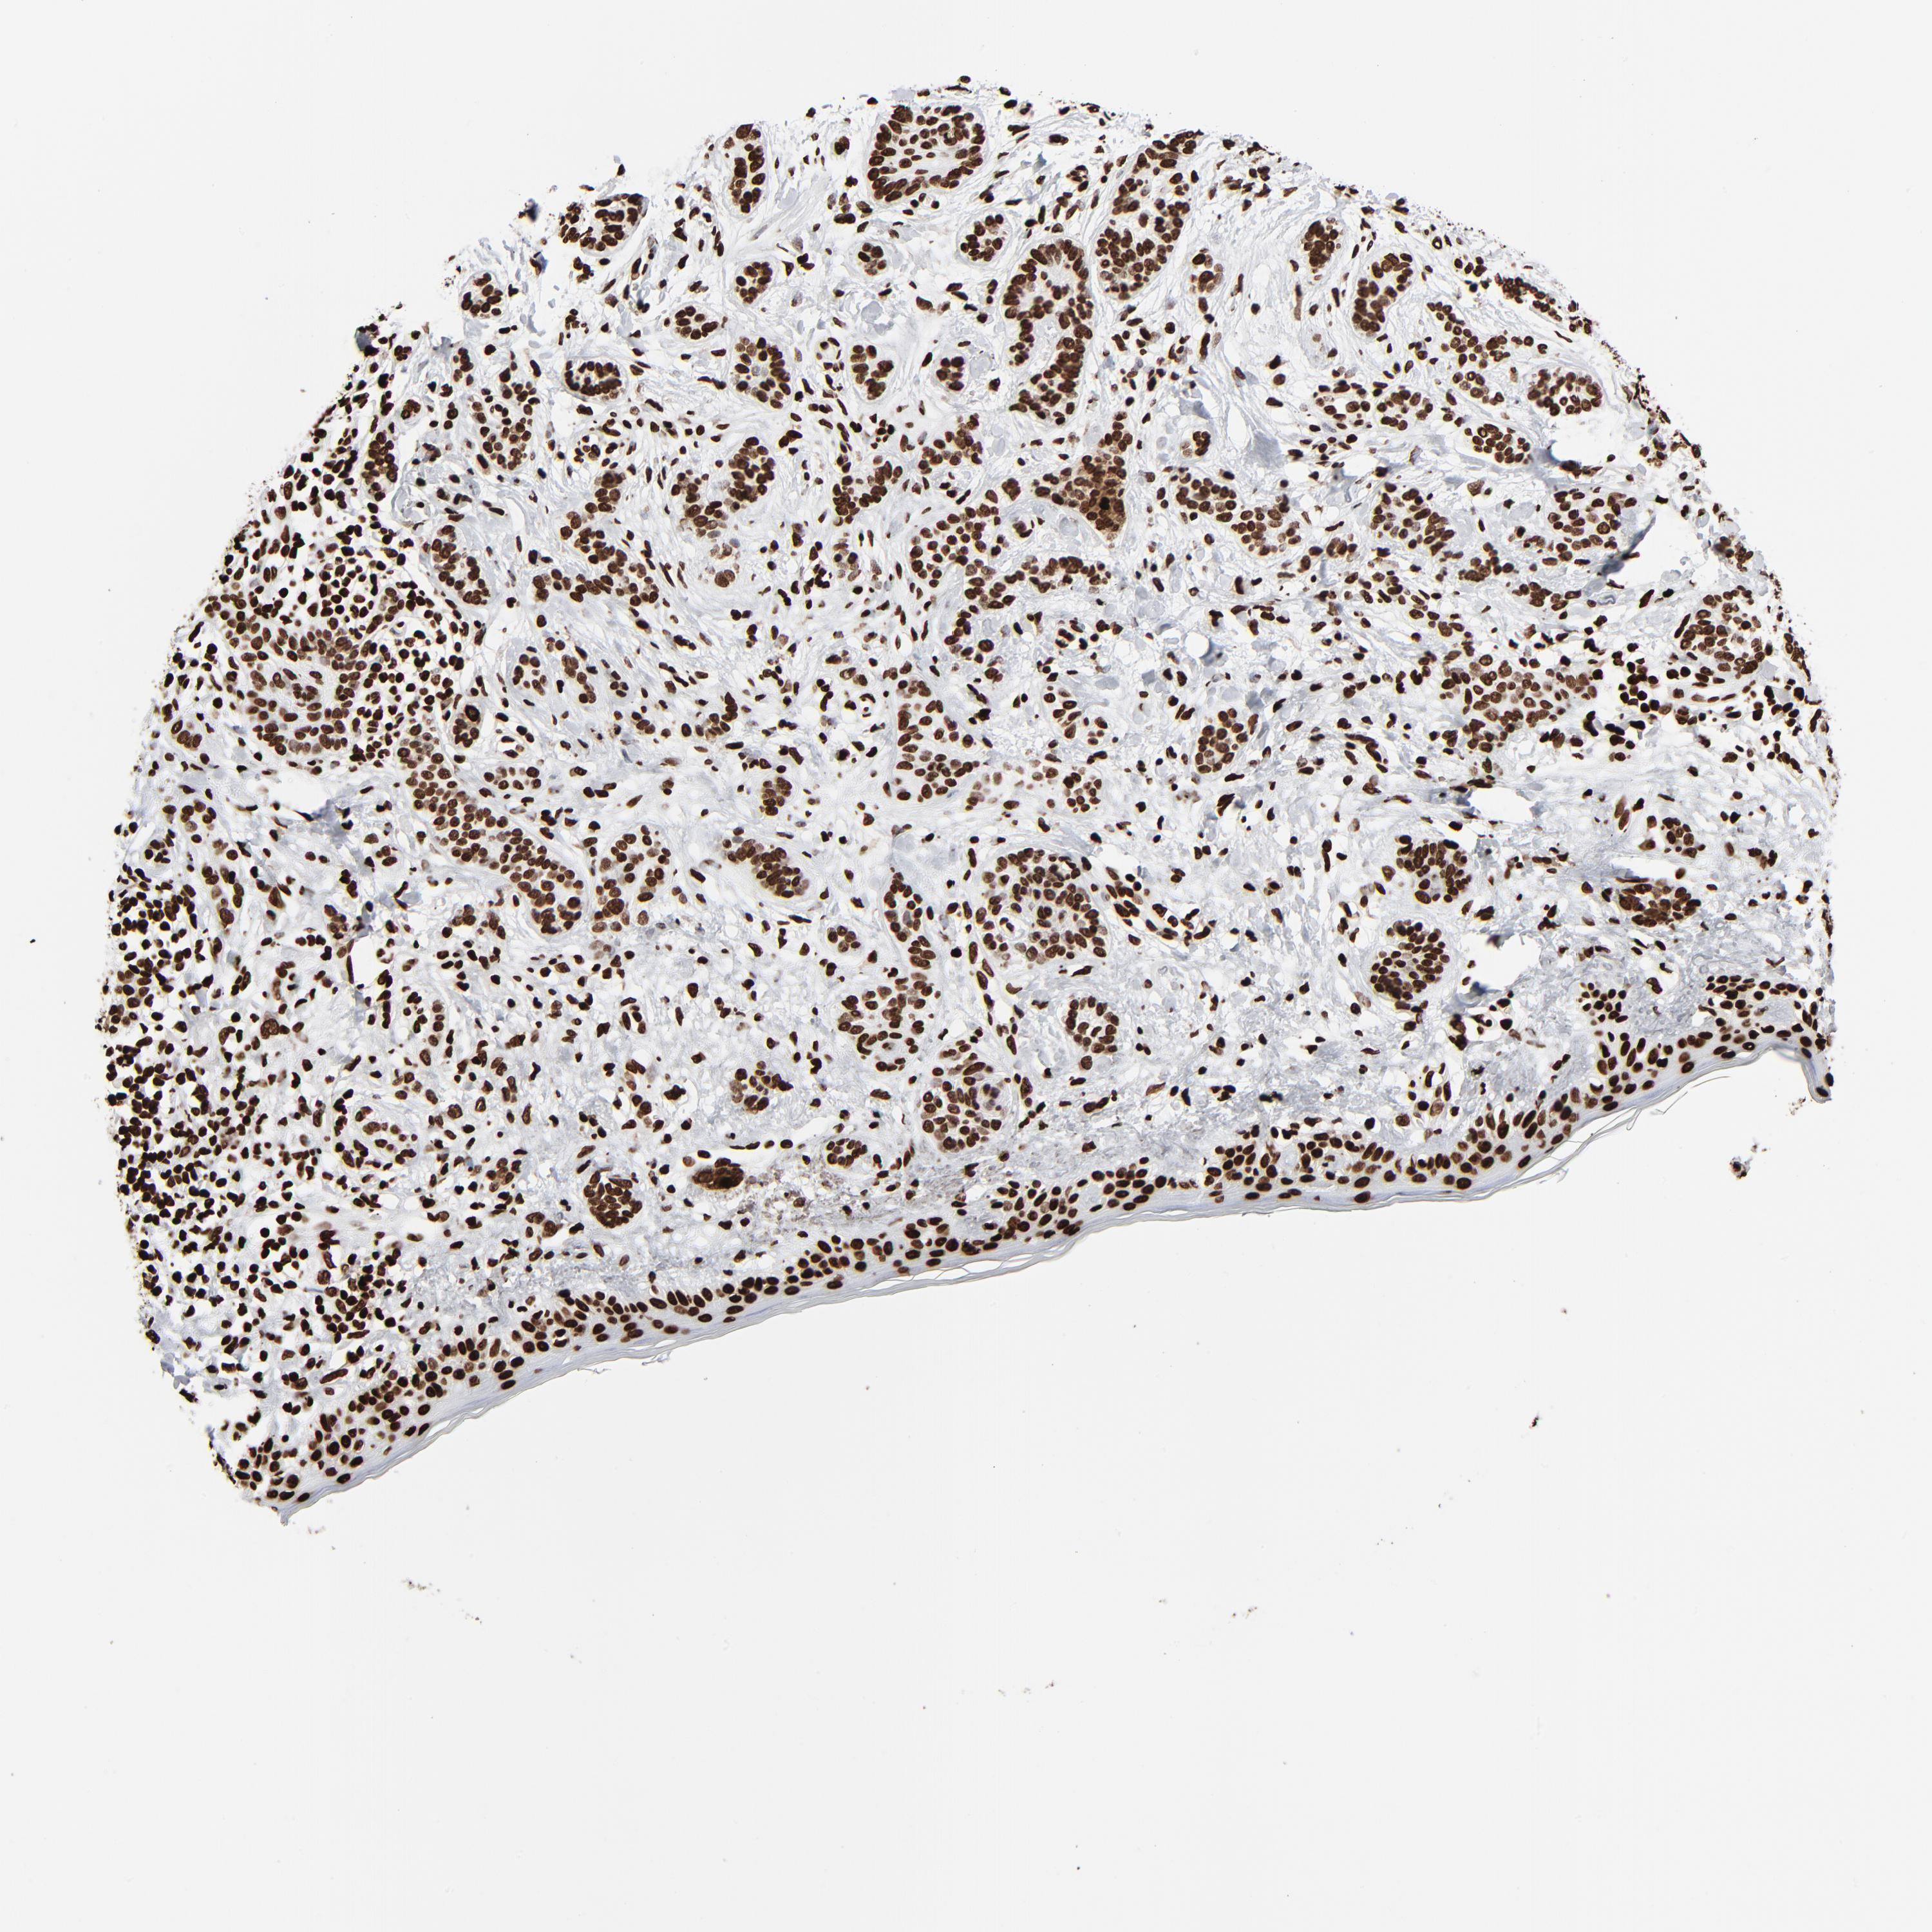

SKIN CANCER - Protein expressioni

A mouse-over function shows sample information and annotation data. Click on an image to view it in a full screen mode. Samples can be filtered based on level of antibody staining by selecting one or several of the following categories: high, medium, low and not detected. The assay and annotation is described here.

Each image is clickable and will lead to virtual microscopy that enables deeper exploration of all samples and also displays staining intensity scores, fraction scores and subcellular localization as well as patient and tissue information for each sample.

Antibody CAB001386

Staining

High

Medium

Low

Not detected

Intensity

Strong

Moderate

Weak

Negative

Quantity

>75%

75%-25%

<25%

None

Location

Nuclear

Cytoplasmic/membranous

Cytoplasmic/membranous,nuclear

Squamous cell carcinoma, NOS

Squamous cell carcinoma, metastatic, NOS